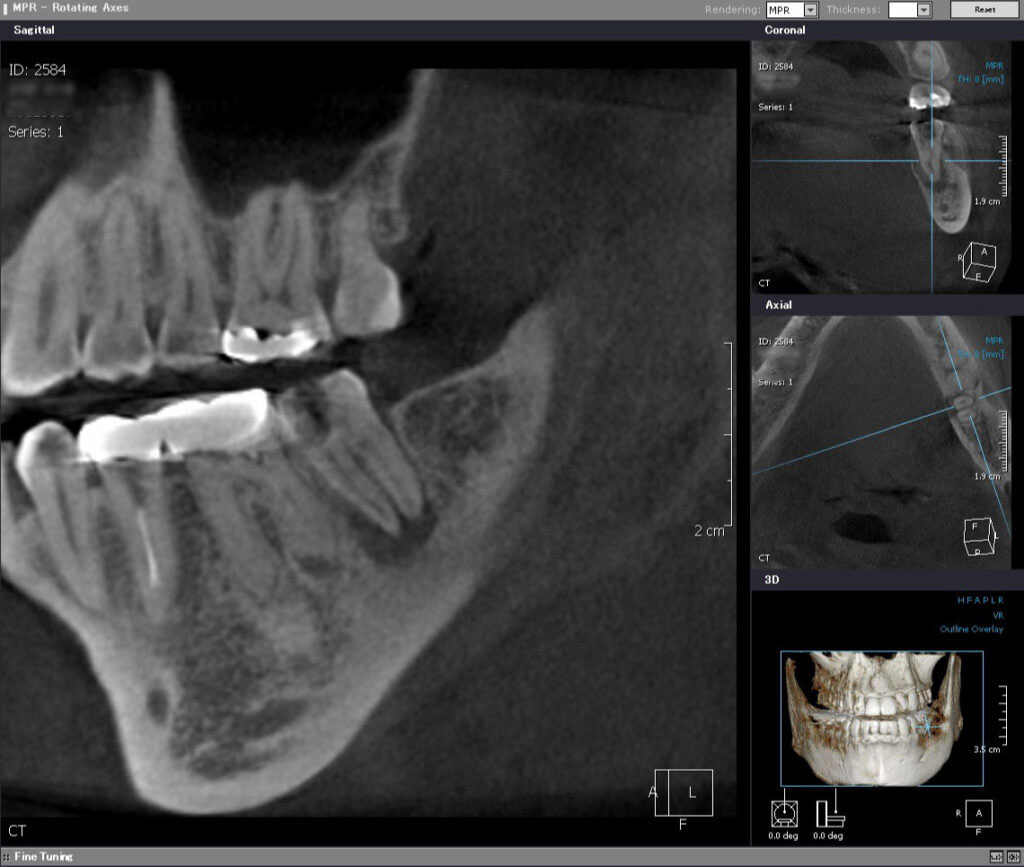

術前CT矢状断

近遠心的(手間から奥に向かって)に、化膿による根っこの先の大きな黒い骨透過像を認めます。手前の左下6番の奥の根っこ(遠心根)の先も化膿していることが分かります。